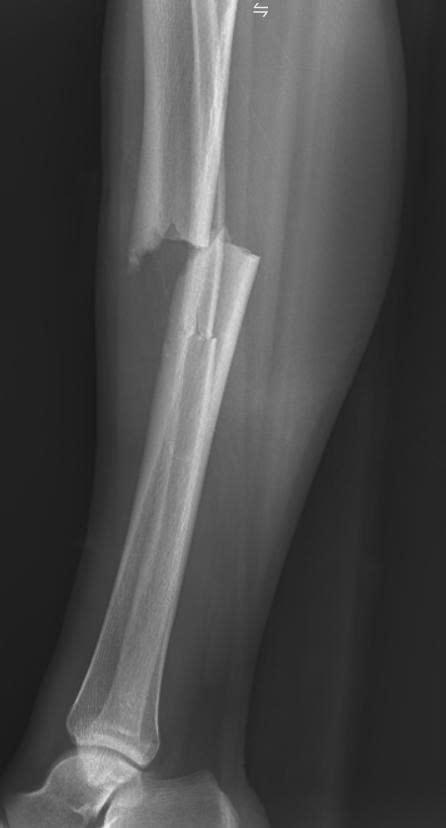

Vừa qua, các bác sĩ khoa Ngoại tổng hợp - Bệnh viện Đa khoa Mê Linh đã tiếp nhận và phẫu thuật thành công cho một trường hợp người bệnh bị gãy hở độ I hai xương cẳng chândo tai nạn giao thông. Đây là dạng chấn thương nghiêm trọng, tiềm ẩn nguy cơ nhiễm trùng và ảnh hưởng lâu dài đến khả năng vận động nếu không được xử trí kịp thời, đúng chuyên môn.

Theo thông tin, người bệnh được gia đình đưa đến cấp cứu vào khoảng 22 giờtrong tình trạng đa chấn thương sau tai nạn giao thông. Ngay khi tiếp nhận, các bác sĩ đã nhanh chóng tiến hành thăm khám, đánh giá toàn diện các tổn thương theo đúng quy trình cấp cứu chấn thương, đồng thời thực hiện các cận lâm sàng cần thiết để xác định chính xác tình trạng gãy xương.